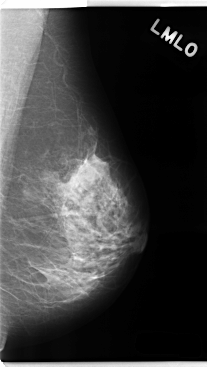

ics_version 1.0 filename C-0234-1 DATE_OF_STUDY 22 12 1994 PATIENT_AGE 40 FILM FILM_TYPE REGULAR DENSITY 2 DATE_DIGITIZED 28 4 1998 DIGITIZER LUMISYS LASER SEQUENCE LEFT_CC LINES 4736 PIXELS_PER_LINE 2240 BITS_PER_PIXEL 12 RESOLUTION 50 NON_OVERLAY LEFT_MLO LINES 4760 PIXELS_PER_LINE 2680 BITS_PER_PIXEL 12 RESOLUTION 50 NON_OVERLAY RIGHT_CC LINES 4760 PIXELS_PER_LINE 2512 BITS_PER_PIXEL 12 RESOLUTION 50 OVERLAY RIGHT_MLO LINES 4688 PIXELS_PER_LINE 2608 BITS_PER_PIXEL 12 RESOLUTION 50 OVERLAY |